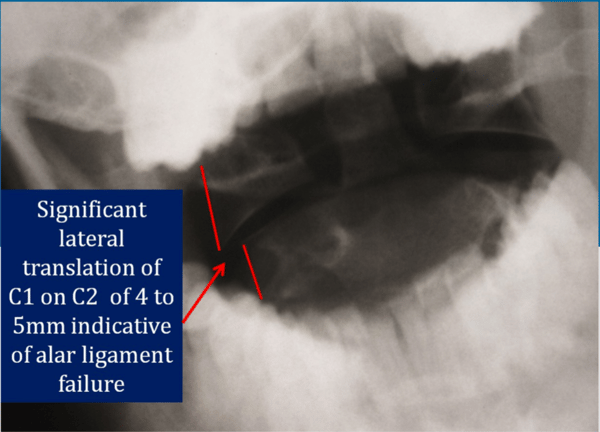

The above x ray is taken through the patient's open mouth as he bends his head to the left.

Normally, the C1 and C2 vertebrae should remain aligned with one another, even as the head is tilted.

This is because the alar and accessory ligaments hold the upper cervical vertebrae in place. These ligaments protect the delicate structures of the spinal cord and surrounding tissue.

As you can see in the above film, there is 4-5 mm of lateral translation of C1 on C2. This represents a severe injury to the upper cervical ligaments, and will be permanent in nature.

This patient will likely require surgical intervention to fuse C1 and C2, and is at significant risk of serious injury should he get in another auto accident, even one at a low speed.